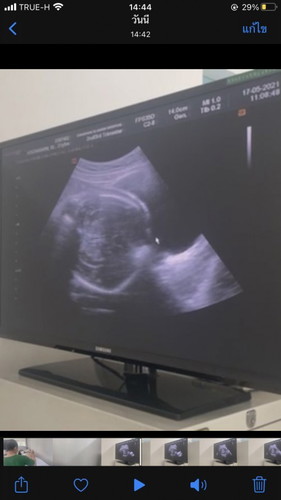

เสี่ยงคลอดก่อนกำหนด33+4w

วันนี้คุณหมอซาวพบว่าหัวน้องจ่อปากมดลูกเตรียมออกแล้วเสี่ยงคลอดก่อนกำหนดสูงแต่น้องน้ำหนักได้แค่1991กรัมเองค่ะหมอบอกอย่าเดินเยอะช่วงนี้ประคองไปอีก2-3อาทิตย์จะดีมากคุณแม่ช่วยแนะนำอาหารเพิ่มน้ำหนักลูกแบบเร่งด่วนหน่อยค่ะ